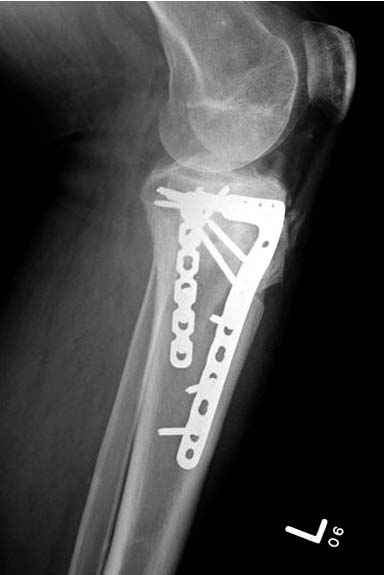

При переломах одного из мыщелков тибиал плато+дополнительный перелом проксимальной трети большеберцовой кости можно применить комбинированный вариант фиксации, т.е. мыщелок винтами или пластиной, а для диафиза можно установить гвоздь. В данном варианте потеряно преимущество гвоздя , из-за серьезной травмы суставной поверхности нельзя нагружать ногу несколько месяцев. А без нагрузки гвоздь просто заполнитель пространства внутри кости!

На вашем место я бы подождал с фиксацией до готовности кожных покровов, и за это время можно было подобрать соответствующий фиксатор, т.е более длинная пластина снаружи и медиальная пластина на апексе перелома как подпорка. Здесь приемлем как раз минимальный доступ.

Здесь пару случаев для сравнения,...в первых 1-4 слайдах метод фиксации одним фиксатором, как видно после 8 месяцев сохранилась ось. С 5 по 9 вариант двумя пластинами...